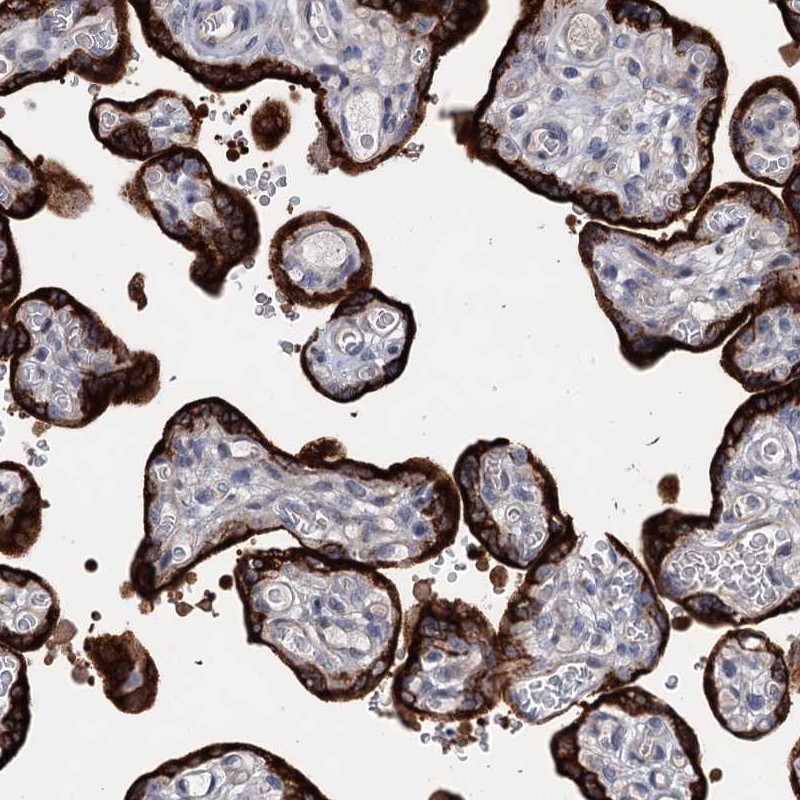

Immunohistochemical staining of human placenta shows strong cytoplasmic positivity in trophoblastic cells.